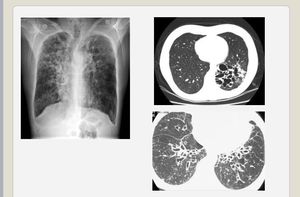

Diagnosis??

tuberculosis

No it is bronchiectasis look to hony comb appearance